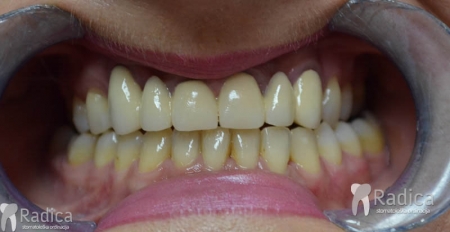

Na sljedećoj slici se mogu vidjeti početak i kraj ortodontske i protetske terapije. Protetske radove radio je dr. Goran Radica.